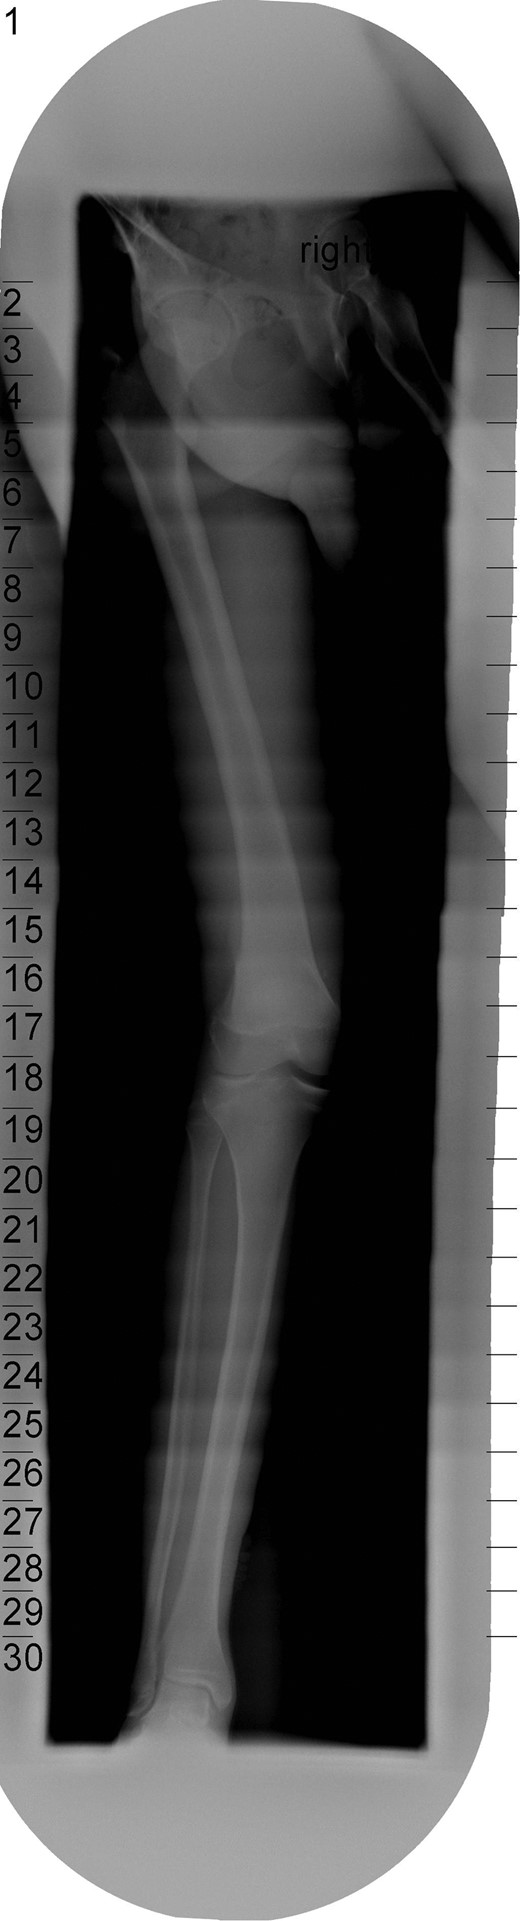

The patient's initial management was non-operative with a period of knee protection with a range of movement brace and intensive rehabilitation. Approximately 3 months after the index injury he returned to competitive football but shortly after his return sustained a further valgus injury and despite further conservative treatment was unable to return to sport. He was referred to our service with ongoing instability symptoms. Upon clinical assessment we noted an asymmetric valgus alignment of the knee and abnormal laxity of the MCL. Radiographic investigations revealed an abnormality of the lateral distal femur and alignment radiographs confirmed the valgus mal-alignment with abnormal opening of the medial tibio-femoral joint space on single-leg stance radiographs (Figs 2–4). We obtained the patient's MRI scan and reviewing this with Radiology colleagues revealed subtle changes of increased lateral femoral physis fluid density on T-2 weighted images consistent with a Salter Harris Type V injury (Fig. 5).

Radiograph demonstrating opening of the medial compartment and increased valgus alignment on single-limb weight bearing.